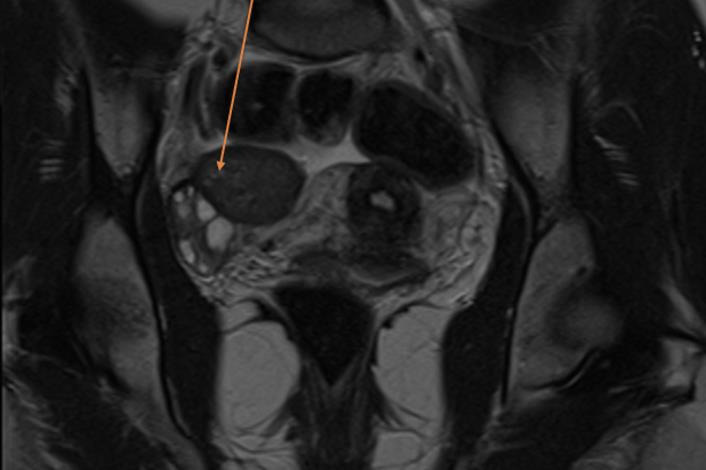

Oxidised regenerated cellulose was introduced 60 years ago to control diffuse bleeding from large surfaces. Although considered safe and effective, foreign body reactions can mimic suspicious masses in several organs. We describe the third case, reported in PubMed, of an oxidised regenerated cellulose-based granuloma mimicking a suspicious ovarian tumour on MRI. During surgery, the diagnosis was suspected by granulomatous tissue and confirmed by pathology. The follow-up after the excision was uneventful. Although a rare complication, physicians should be aware of this presentation and of the recommendation to remove excess Surgicel after the bleeding has stopped.